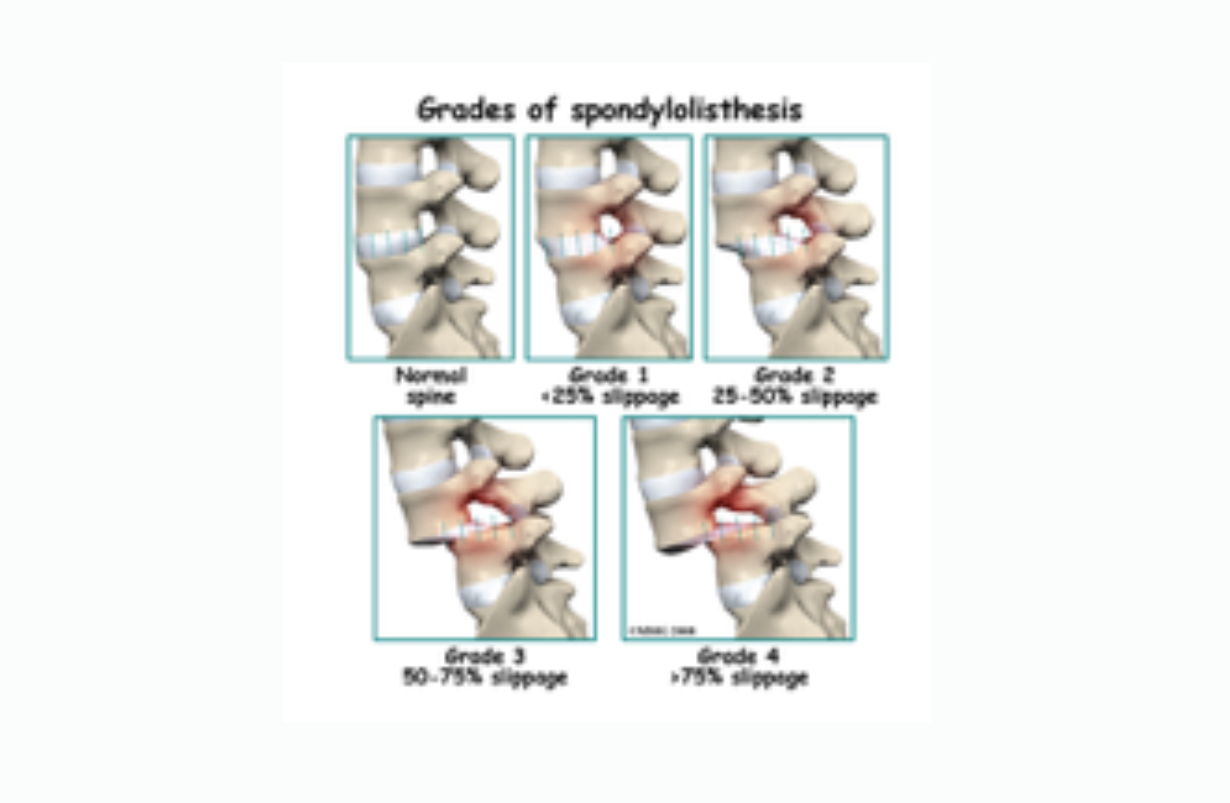

Anterolisthesis

Forward sliding of one vertebra on the one below it: Grade I - 1-25% Grade II - 25 - 50% Grade III - 50 - 75% Grade IV - 75 -100% The vast majority are Grade I, but even that can be significant if there is also a bulging disc, arthritis, or other factors that narrow the central spinal canal or the narrow neuroforamina through which nerve roots pass on their way to the legs or arms.

Spondylolisthesis

Spondylolisthesis occurs when one vertebra slides forward, backward or to the side, relative to the one directly below it. This slippage can occur in the cervical, thoracic (much less commonly) or the lumbar spine, and is generally forward slippage, anterolisthesis. Retrolisthesis is backward slippage of the vertebra above, and lateral listhesis involves slippage to one side or the other. Regardless of the direction, spondylolisthesis is graded in one way: Grade I: 0 - 24.9% of the lower vertebra is uncovered, Grade II: 25 - 49.9%, Grade III 50 -74.9%, and Grade IV: 75% or more. Anterolisthesis and retrolisthesis can cause all the neurological symptoms of a herniated disc or spinal stenosis, because it can narrow the spinal canal nd also shrink the opening through which the nerve root leaves the spinal cord (neuroforamen). .Generally Grade I is painless, though there are exceptions when e.g., the facet joints are swollen from arthritis, or there is a bulging or herniated disc narrowing the opening in the spine through which nerve roots exits (neuroforamina). However even Grade I, and certainly higher grades can leave the intervertebral disc uncovered by the vertebra above, and this can lead to paraesthesias, numbness, pain and weakness, and even bowel or bladder symptoms in extreme cases. Most cases are traumatic in origin, but some authorities assert that it can be congenital, particularly when the bone connecting the facets to the vertebral body (the pars interarticularis) is fractured. Yoga is particularly useful in the most common type of spondylolisthesis, anterolistghesis. In general with anterolisthesis, the strategy is to move back the forward-slid vertebra. Abdominal strengthening and forward bending, making the spine as long as possible, are the poses that do this. Retrolisthesis is treated just the opposite way: strengthening the quadratus lumborum muscles, and doing back extension poses. Lateral listhesis is rarely symptomatic, although it makes the yogic treatment of scoliosis more difficult. See 'scoliosis' for details.